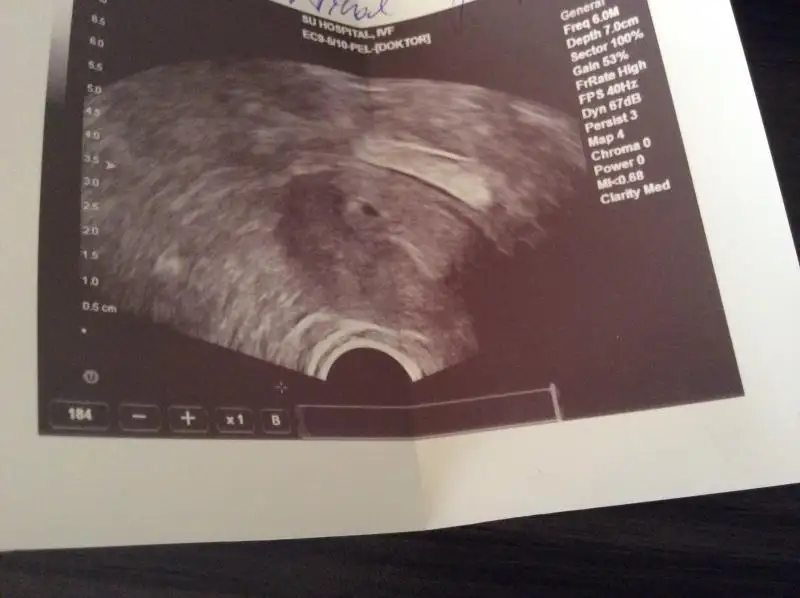

Kızlar Buda benim kesecik😊bugün. 5+1 haftalık.kese kaç mm ben anlamadım bileniniz varsa yanda yazan rakamlardan beni de bilgilendirebilir mi?

canım senin resimde kese ebatı yazmıyor.benim ilkinde GS 0,38 cm GS0,29 cm olarak kesenin 2 taraftan ölçüm boyutu yazıyordu.mm ye çevirdiğimde de 3,8 x 2,9 mm oluyor